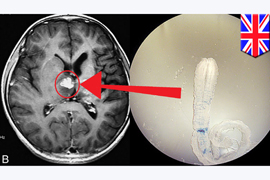

Չորս տարի առաջ բրիտանացին, վերադառնալով դեպի Չինաստան, Հարավային Կորեա, Ճապոնիա եւ Թայլանդ ուղեւորությունից, տարօրինակ գանգատներով դիմել է բժիշկներին: Նրանք տուբերկուլյոզի դեմ բուժում են սկսել, բայց տարօրինակ ախտանշանները չեն անցել, եւ 2013 թ. ցնցումների, գլխացավերի ու ոտքերում թուլության գանգատներով նա նորից դիմել է քեմբրիջյան Addenbrookes Hospital կլինիկա:

Պարզվել է, որ բոլոր այդ ախտանշանների պատճառը նրա ուղեղում գտնվող եւ դրանով սնվող Spirometra հսկայական երիզորդն է: Բժիշկներն ստիպված են եղել երիզորդին վիրահատական միջամտությամբ հեռացնել, քանի որ ոչ մի այլ «բուժում» նման դեպքում չի եղել:

1953-2013 թթ. այդպիսի որդերով վարակվելու միայն մոտ 300 դեպք է հայտնաբերվել: Քանի որ որդը հազվագյուտ է, նրա մասին գրեթե ոչինչ չգիտեն: Հայտնի է միայն, որ նրանք սովորաբար բնակվում են կատուների եւ շների աղիքներում: Այդ կենդանիների կղանքում հայտնված դրանց ձվերը կարող են ջուրն ընկնել, իսկ ջրից էլ փոխանցվել մարդուն:

Բացառված չէ, որ բրիտանացուն, ում անունը հասկանալի պատճառներով չի բացահայտվում, որդը հենց այդ ճանապարհով էլ փոխանցվել է. հավանաբար, որդը հայտնվել է նրա մարմնում այն ժամանակ, երբ վերջինս լճում լողալիս է եղել եւ պատահաբար ջուր է կուլ տվել: